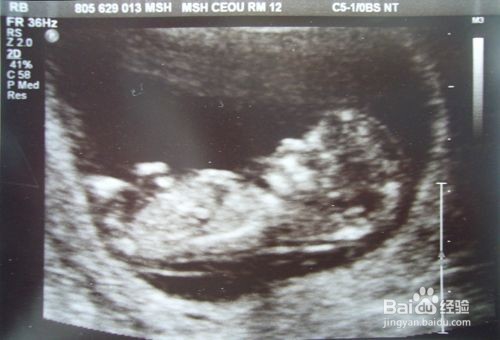

2、检查时间:早唐(NT):孕早期9-13周

3、检查方式:早唐B超检测颈部透明带厚度(NT值)

5、正常值标准:NT小于2.5mm